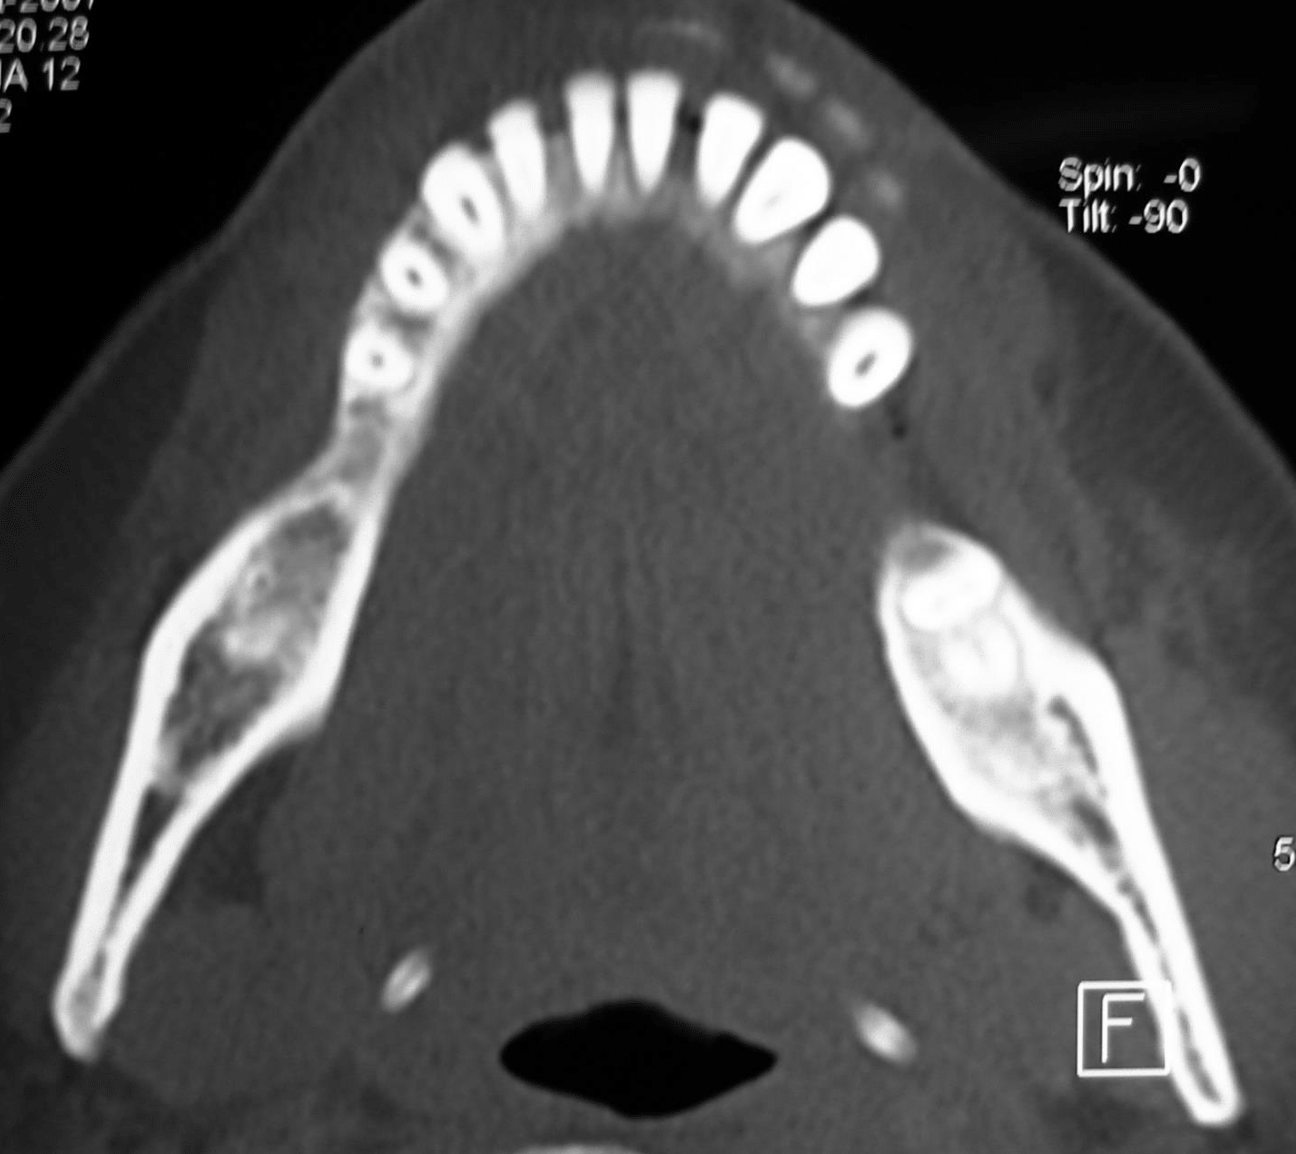

Preoperative radiographic examination including panoramic X-ray and C.T for evaluation of mandibular bone invasion by the lesion and evaluation of the neck lymph nodes (Figure 2A, B, C). Both the mandibular bone and neck lymph nodes were free. Whole body scan with Technetium-99m radiopharmaceuticals imaging was negative (Figure 2D). Clinical stage according to TNM system was T1N0M0.

Figure 2b CT axial view for evaluation of bone invasion by GSCC.